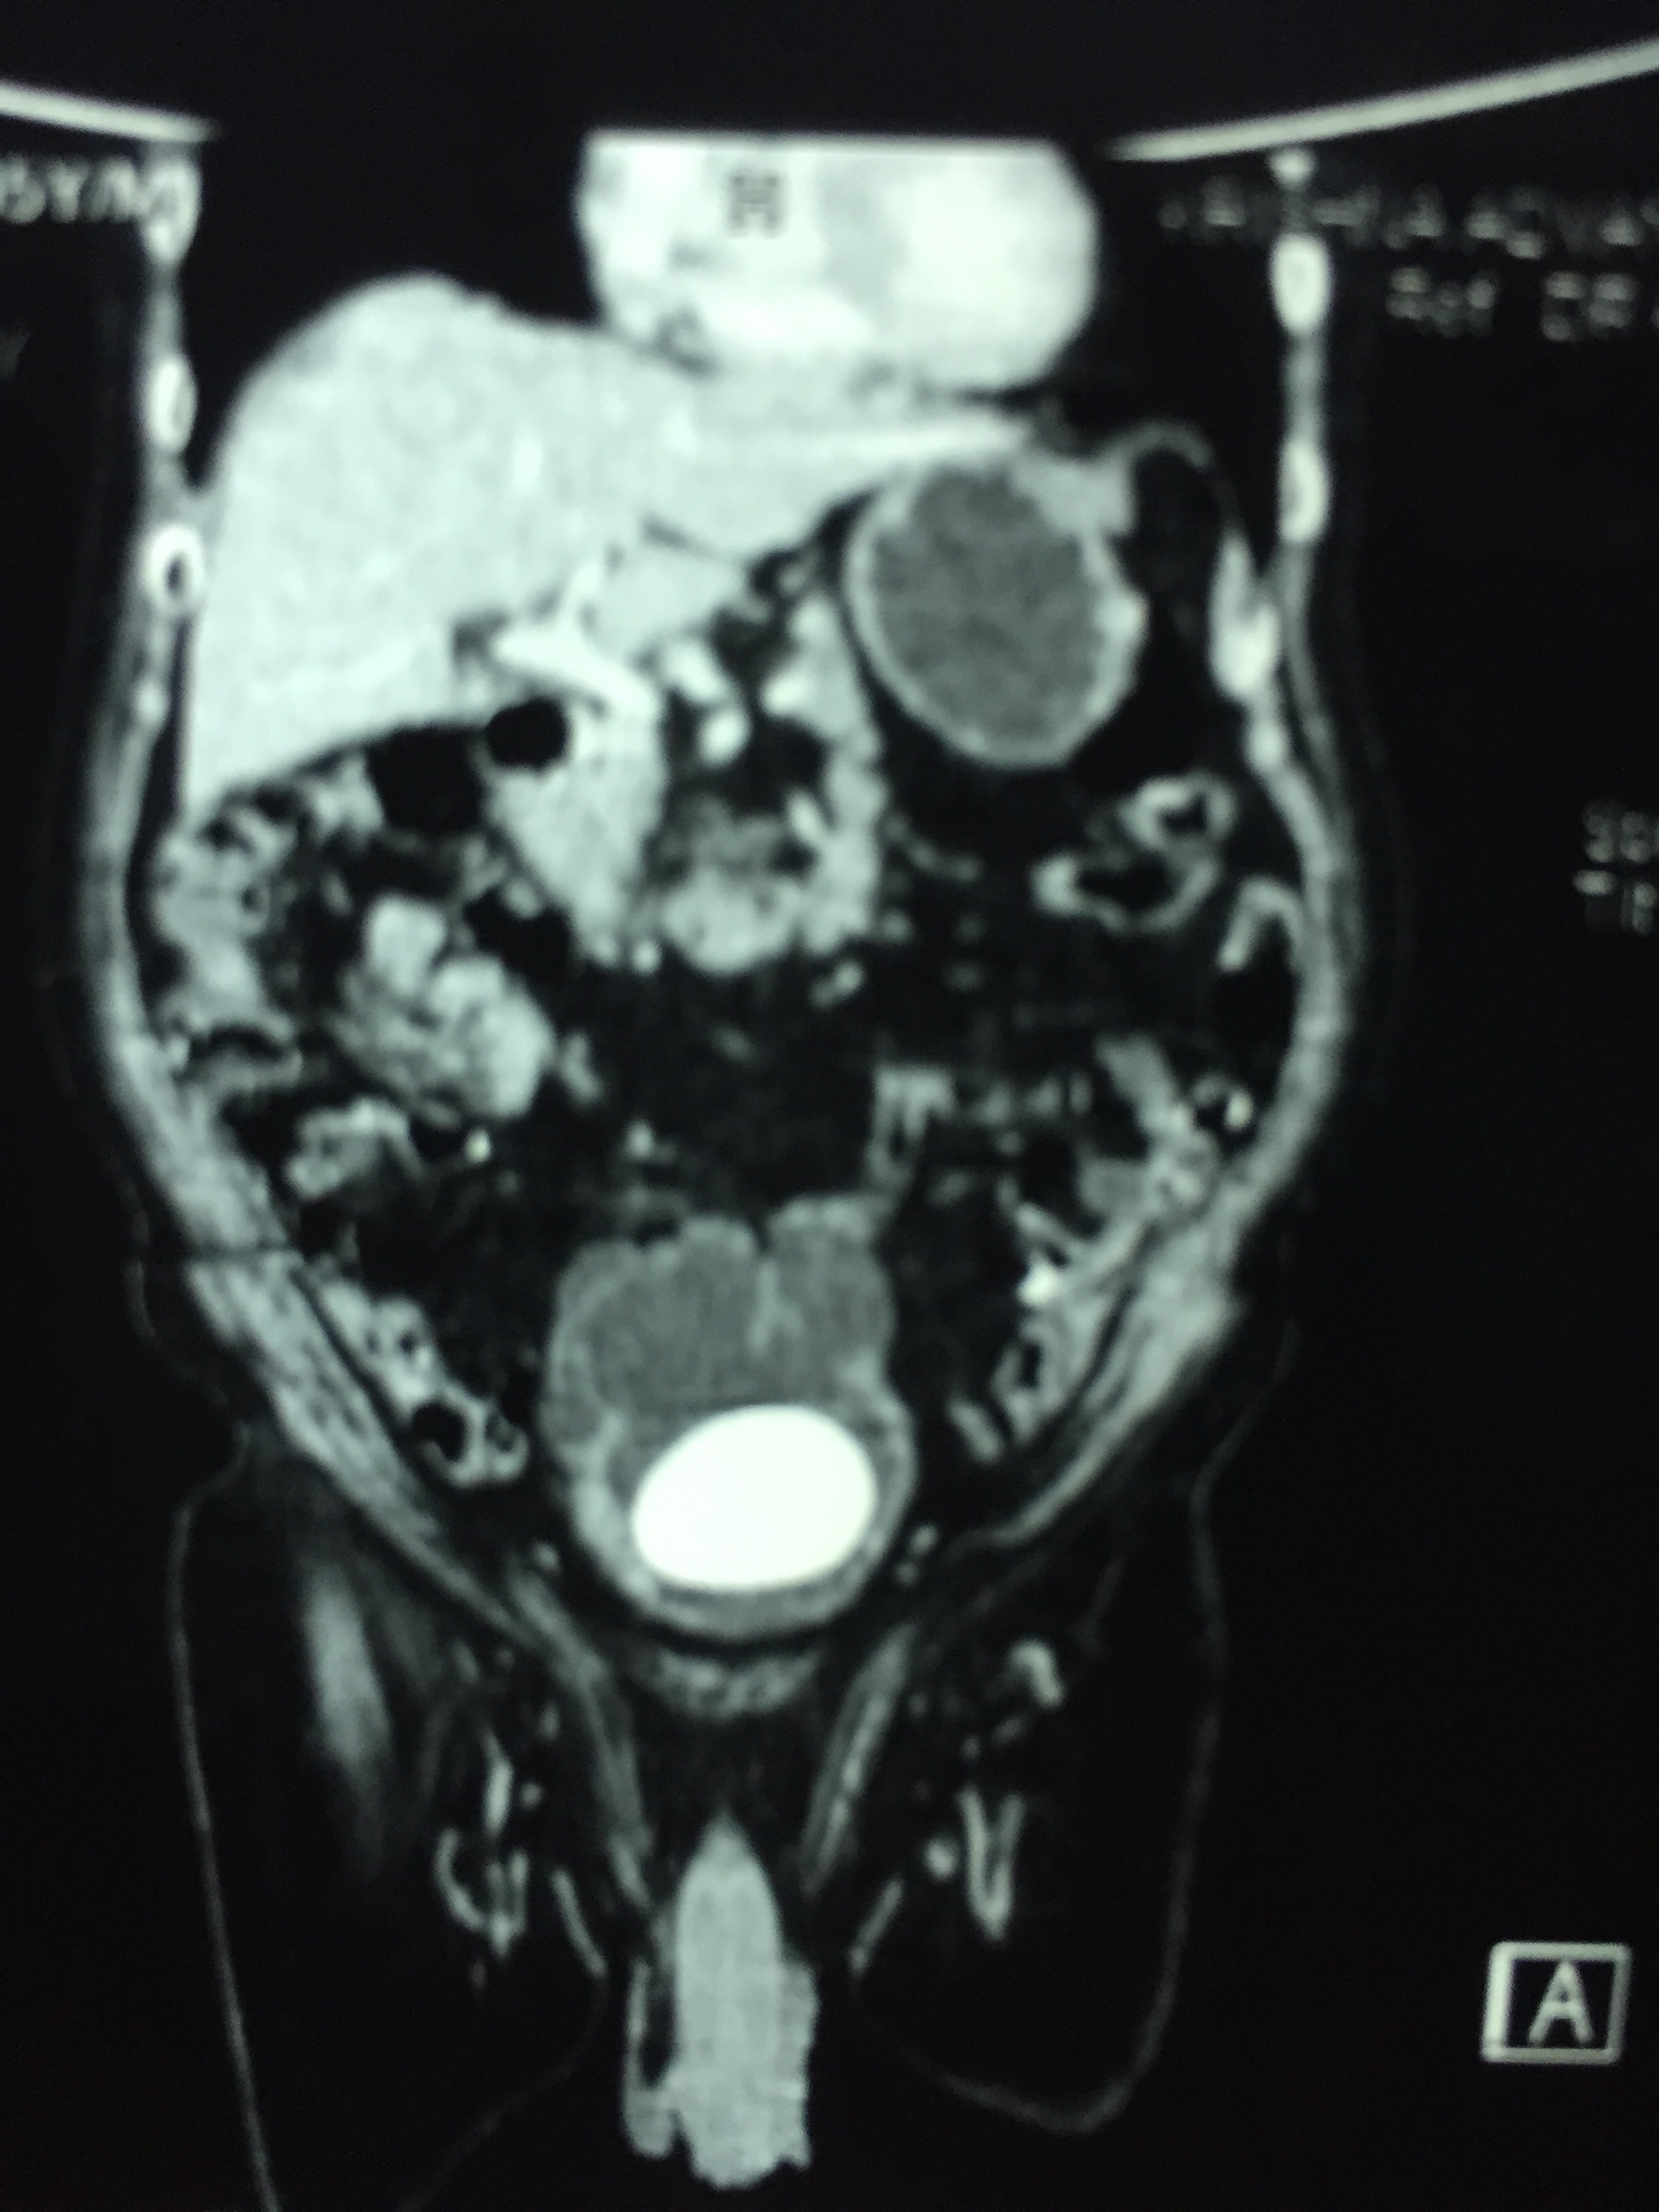

CT scan confirmed the ultrasound findings :

LARGE CALCULUS IN THE URINARY BLADDER WITH MULTIPLE DIVERTICULAE IN THE BLADDER “

The X-ray and the CT scan pictures are given below.